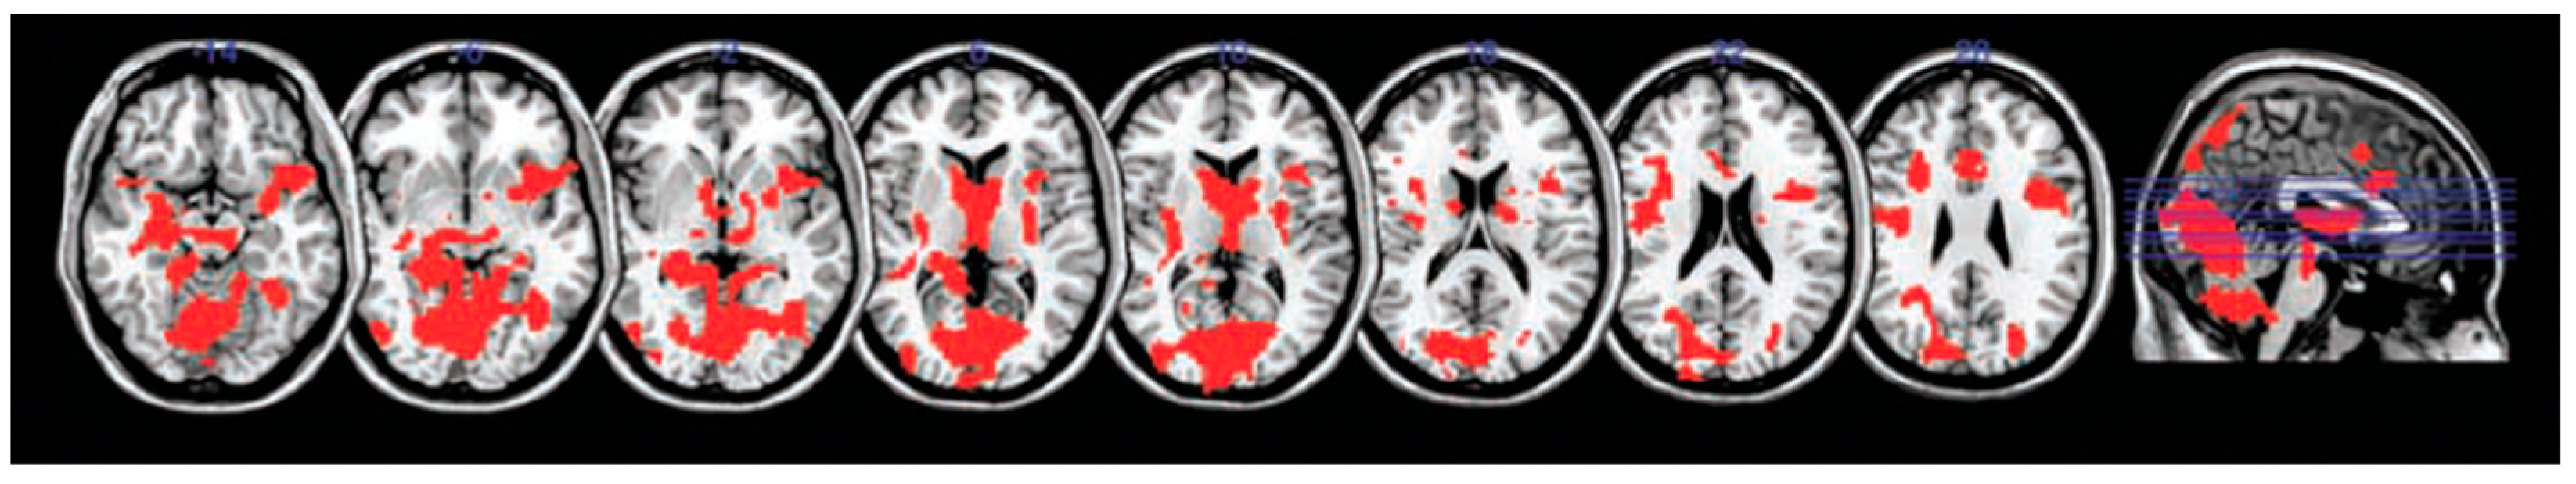

- Sekeres, M.J.; Winocur, G.; Moscovitch, M.; Anderson, J.A.E.; Pishdadian, S.; Martin Wojtowicz, J.; St-Laurent, M.; McAndrews, M.P.; Grady, C.L. Changes in Patterns of Neural Activity Underlie a Time-Dependent Transformation of Memory in Rats and Humans. Hippocampus 2018, 28, 745–764. [Google Scholar] [CrossRef] [PubMed]